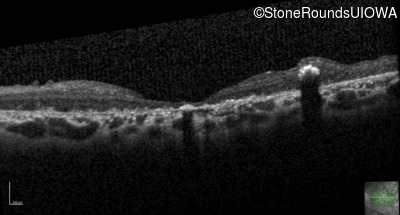

Optical Coherence Tomography - Right - Count Fingers 3'

Exemplar / OCT Stack